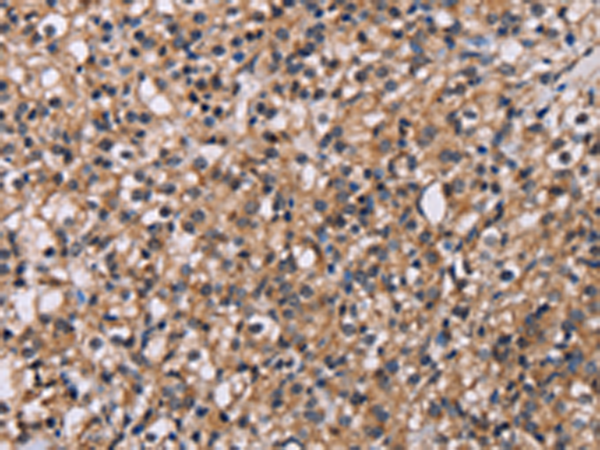

分类: 科研抗体货号: P01655别名: MPPB; P-52; MPP11; MPPP52; Beta-MPP应用: WB,IHC反应种属: Human, Mouse, Rat